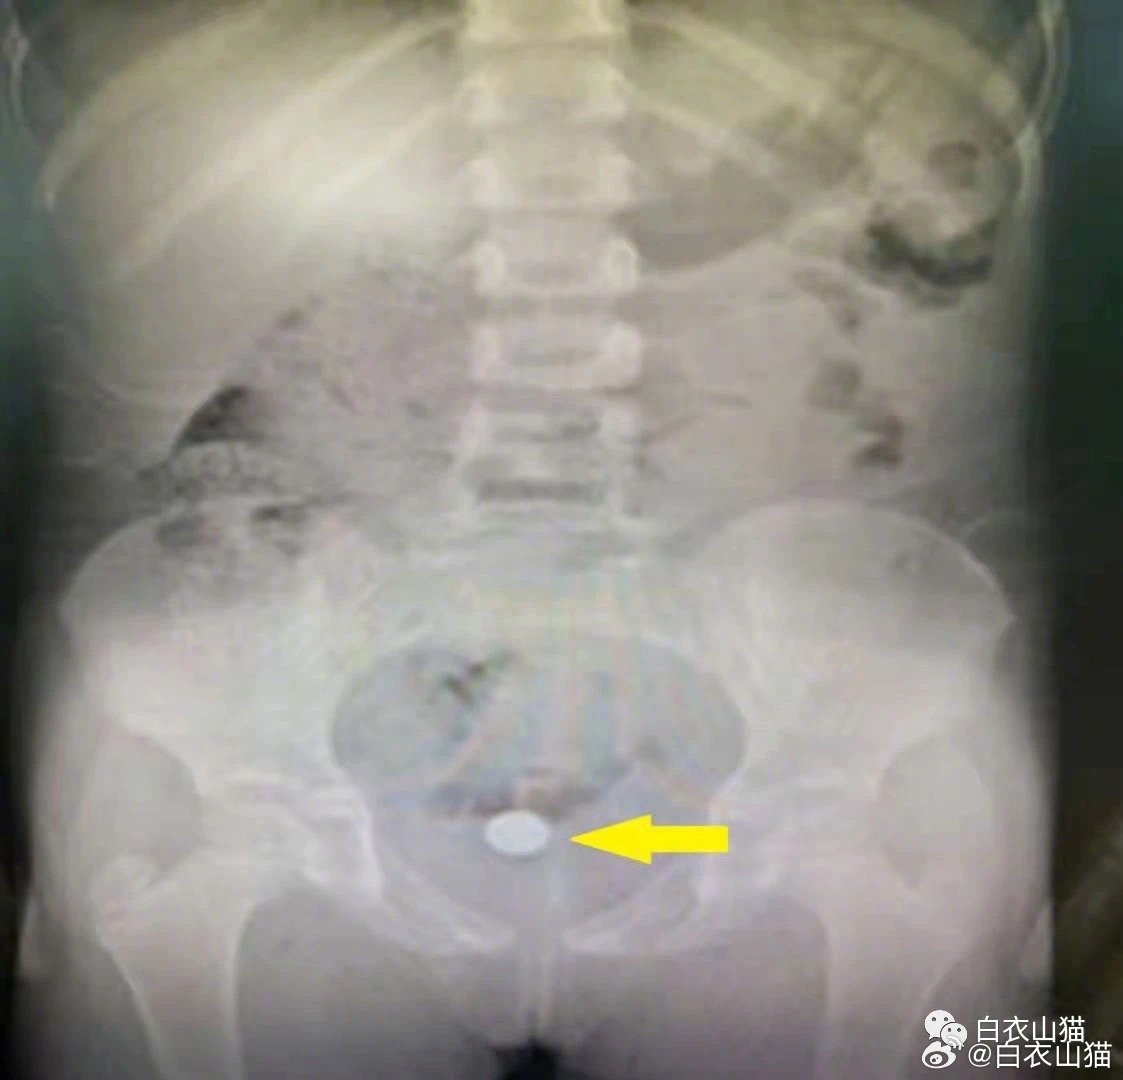

曾经有这么一个女病人,她出现了反复发作的膀胱炎和尿路感染,结果医生发现,她的膀胱里,有个巨大的结石,结石中央,依稀可以看出是个玻璃杯。

图片2

患者膀胱内的巨大结石。